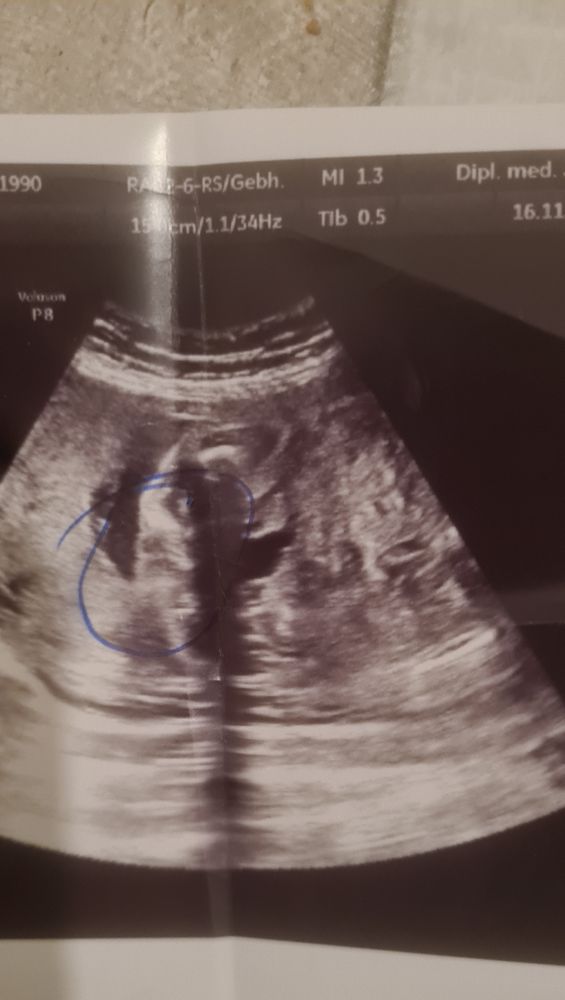

Изображение Моя в 18 недель. По расположению похожа на ваше фото.

Мадина Мадина, тут ведь и такое бывает, что на всех УЗИ видят мальчика, а появляется девочка)) можно попробовать сделать 3Д УЗИ. Там точно пол покажет, да и личико увидите

Сестры с разницей 2 года Сходили на УЗИ))))